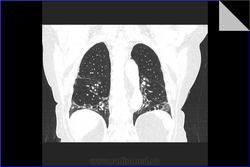

Идиопатический фиброзирующий альвеолит. Пациентке 79 лет. Диагноз поставлен 3 года назад. Лечится гормонами. Клинически за 3 года наросла одышка. Данные прошлых исследований не предоставлены. Заинтересовали размеры легочной артерии. Основной ствол - 37 мм (N=29 мм), правая ветвь 33 мм (N=24 мм), левая ветвь 28 мм (N=28 мм). Интересно, почему степень расширения левой легочной артерии отстает от правой и основного ствола. Обусловлено ли это разными углами отхождения ветвей или может косвенно характеризовать степень вовлеченности легочной ткани каждого легкого в фиброзирующий процесс?

Идиопатический фиброзирующий альвеолит. Пациентке 79 лет. Диагноз поставлен 3 года назад. Лечится гормонами. Клинически за 3 года наросла одышка. Данные прошлых исследований не предоставлены. Заинтересовали размеры легочной артерии. Основной ствол - 37 мм (N=29 мм), правая ветвь 33 мм (N=24 мм), левая ветвь 28 мм (N=28 мм). Интересно, почему степень расширения левой легочной артерии отстает от правой и основного ствола. Обусловлено ли это разными углами отхождения ветвей или может косвенно характеризовать степень вовлеченности легочной ткани каждого легкого в фиброзирующий процесс?

Для легочного идиопатического фиброза = криптогенного фиброзирующего альвеолита изменения не выражены - может, адекватная терапия. Либо одышка и ДН по другой причине. Если брали биопсию - вопросов нет, а если нет, то есть)))